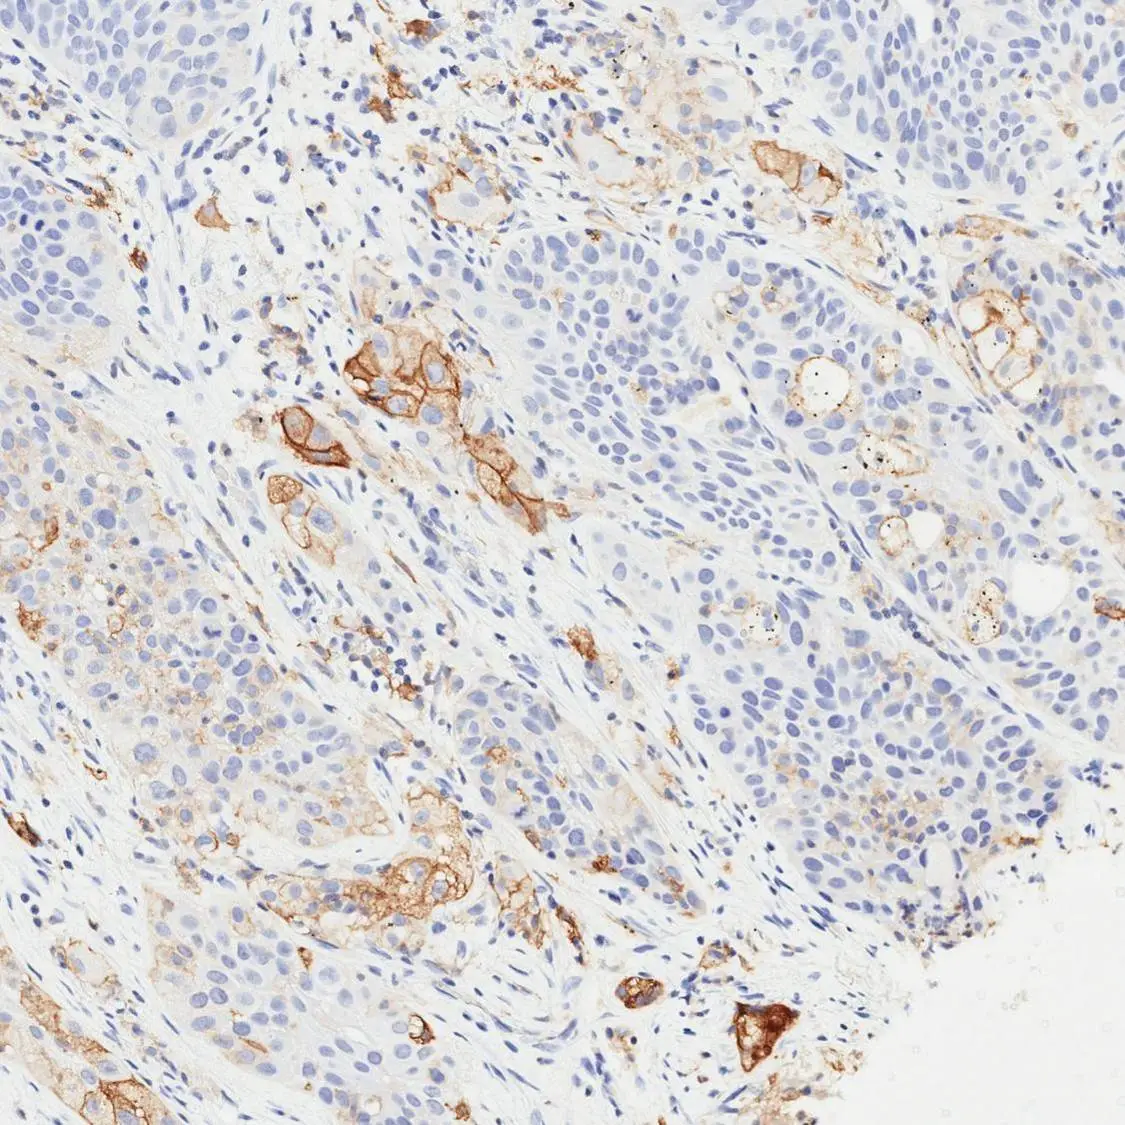

Optimal staining result of human NSCLC, tissue core no. 6, using PD-L1 antibody [H302] HistoMAX™ on Leica Bond III, following the vendor recommended protocol settings.

Distinct membranous reactivity ranging from weak to strong intensity is demonstrated across virtually all tumor cells. Based on this diffuse expression pattern, the tumor is categorized as TPS High (≥50%).